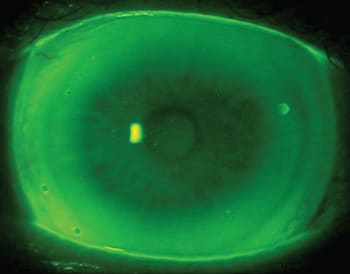

An exciting area of potential GP multifocal application pertains to scleral designs. Combining the initial comfort of a scleral design with multifocal correction could entice new wearers into multifocal lenses. The Digiform and Tru-Scleral designs (Truform Optics) as well as the So2Clear Progressive (Dakota Sciences/Art Optical/Metro Optics) (Figure 1) have center-near designs, while the Dyna Semi Scleral (Lens Dynamics) has an aspheric design (Potter, 2012). Blanchard is also developing a multifocal scleral design.

Figure 1. The So2 Clear Progressive Design (Dakota Sciences/Art Optical/Metro Optics). COURTESY OF JASON JEDLICKA, OD